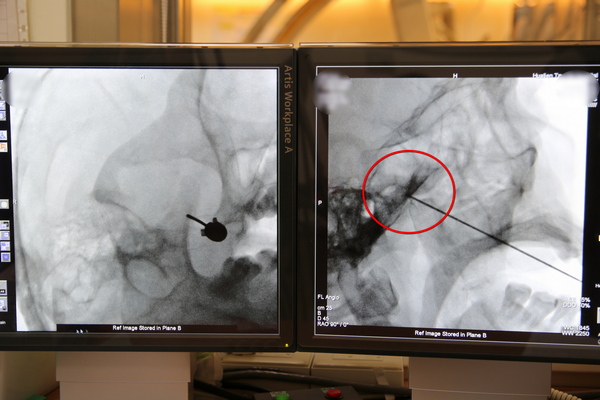

初期先以高頻熱凝療法治療林先生右臉的三叉神經周邊,但效果只能持續約三個月,去年十一月開始深入到三叉神經的神經節灼燒。王柏凱主任表示,高能量透過電擊針尖端引發電磁場產生熱能,設定溫度後調節神經痛,止痛的效果能持續半年,治療的藥物也能減少許多,讓病人生活品質提升,半年後若是疼痛感加劇,病人可以再次進行高頻熱凝療法治療。

右圖:麻醉部疼痛科主任王柏凱使用高頻熱凝療法將電擊針深入至三叉神經的神經節治療。